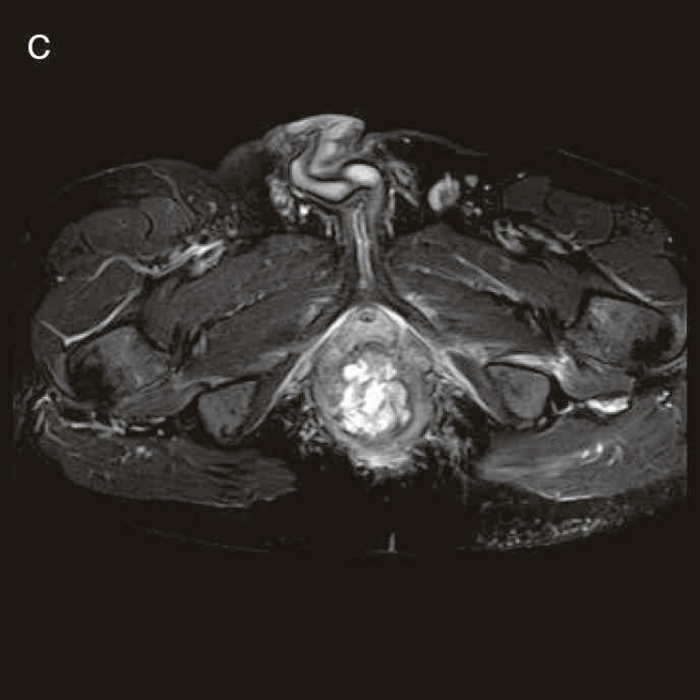

図27 CD直腸肛門部癌の骨盤造影MRI検査像

直腸内に増強効果を受ける分葉状の腫瘤を認める。

内視鏡以外の画像診断には,超音波検査,CT検査,MRI検査などがあるが,CD関連腫瘍に関する診断は,やはり未確立である4)。こうしたcross sectional imagingにおいては,CDの炎症による腫瘤や膿瘍との鑑別が課題となる5)。CD関連消化管癌では病変が房状を呈することがあるが(図27),早期の病変を診断することは困難である。臨床では,痔瘻や肛門周囲膿瘍の評価のためのcross sectional imagingによる検査でCD関連消化管癌の可能性がある所見を拾い上げられるかがポイントとなるが,確定診断後に画像診断所見を見直した際に,所見に気付くことも少なくない。また確定診断のためには,内視鏡検査による生検や外科的な生検か細胞診を行う必要がある。